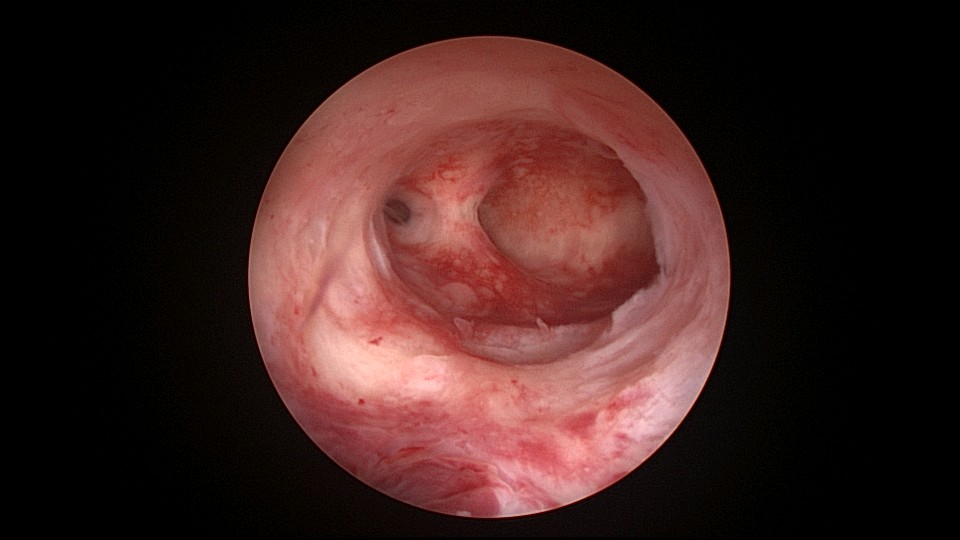

患者42,G3P1,顺产1次。子宫腺肌症伴腺肌瘤,逐渐加重的痛经,2024年11月起皮下注射亮丙瑞林3个周期,出现潮热出汗症状。2025年4月,要求放置曼月乐环并固定,子宫后位,宫深9cm,宫腔上段右侧粘连,宫腔下段宽大。4-0不可吸收线将曼月乐缝合固定于宫腔上段后壁,缝线上靠近曼月乐间距1cm左右打3个结,缝合1针,将1个线结拉过缝合处肌层,利用子宫肌层线结卡压固定曼月乐,避免打结推结。术后多次复查B超,曼月乐位置正常,环顶端距宫底1.6cm。